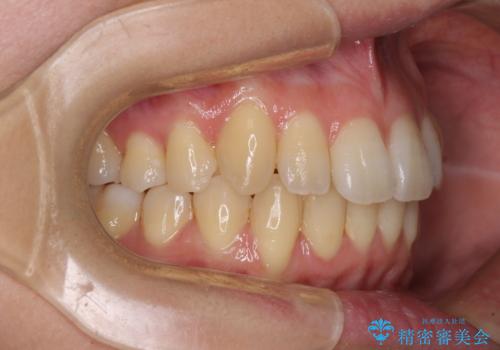

- 上の前歯、および下の歯列全体のでこぼこを気にして来院された患者様です。

インビザラインを用い、IPR(歯と歯の間を削る)と歯列全体を後方に移動させることで、歯並びを整えていくこととしました。

歯列全体を後方に移動させるため、下顎の親知らず2本を抜歯することとしました。